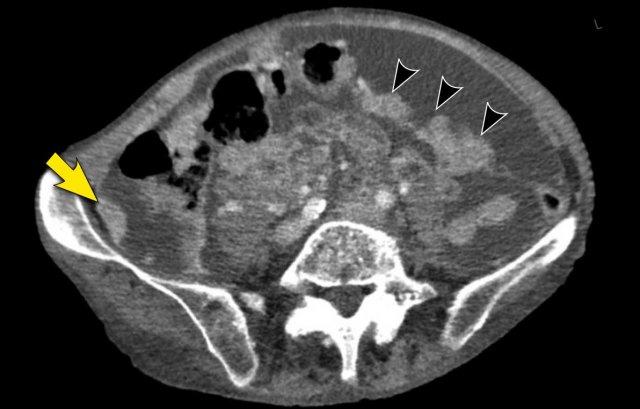

Mạc nối bánh

Mạc nối là một trong những cấu trúc trong ổ bụng đầu tiên bị xâm lấn bởi ung thư phúc mạc.

Hình ảnh gọi là “mạc nối bánh” (omental cake) là kết quả của các nốt khối u lan rộng trong mạc nối lớn.

Tổn thương này có hình ảnh rất điển hình trên cả siêu âm và CT.

Hình ảnh

Hình ảnh CT của mạc nối bánh nổi trong dịch cổ trướng (mũi tên).

Mạc nối nằm ở bụng trái, trải dài từ bờ ngoài dạ dày xuống phía dưới.

Hình ảnh cho thấy cấu trúc dạng nốt không đồng nhất rõ rệt, điển hình của mạc nối bánh.

Các chấm trắng trong mạc nối có thể là các mạch máu.